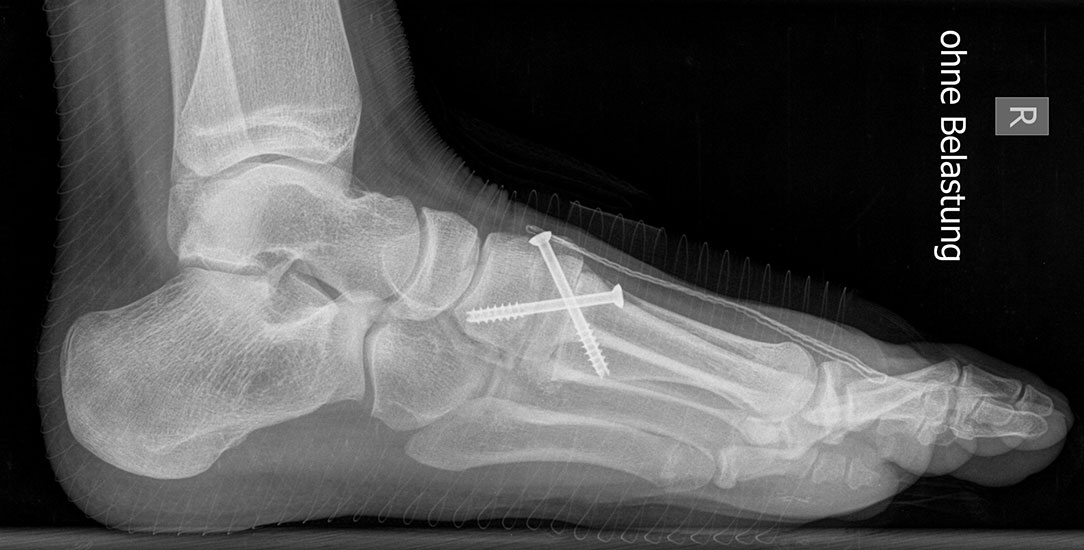

Röntgen

Standard ist die belastete Röntgenaufnahme des Fußes dorso-plantar und seitlich. Günstig ist eine Röhrenkippung von 10°-20°, um die Gelenke der Lisfranc-Linie einsehen zu können.

Ergänzend kann eine Schrägaufnahme hilfreich sein. Bei Metatarsalgien oder Pathologien der Sesambeine liefert die Sprinteraufnahme zusätzliche Informationen. Bei einer Pes planovalgus Fehlstellung wird ergänzend ein Saltzman view durchgeführt.

• Nach Schluss der Wachstumsfugen: TMT I Arthrodese nach Lapidus 2425